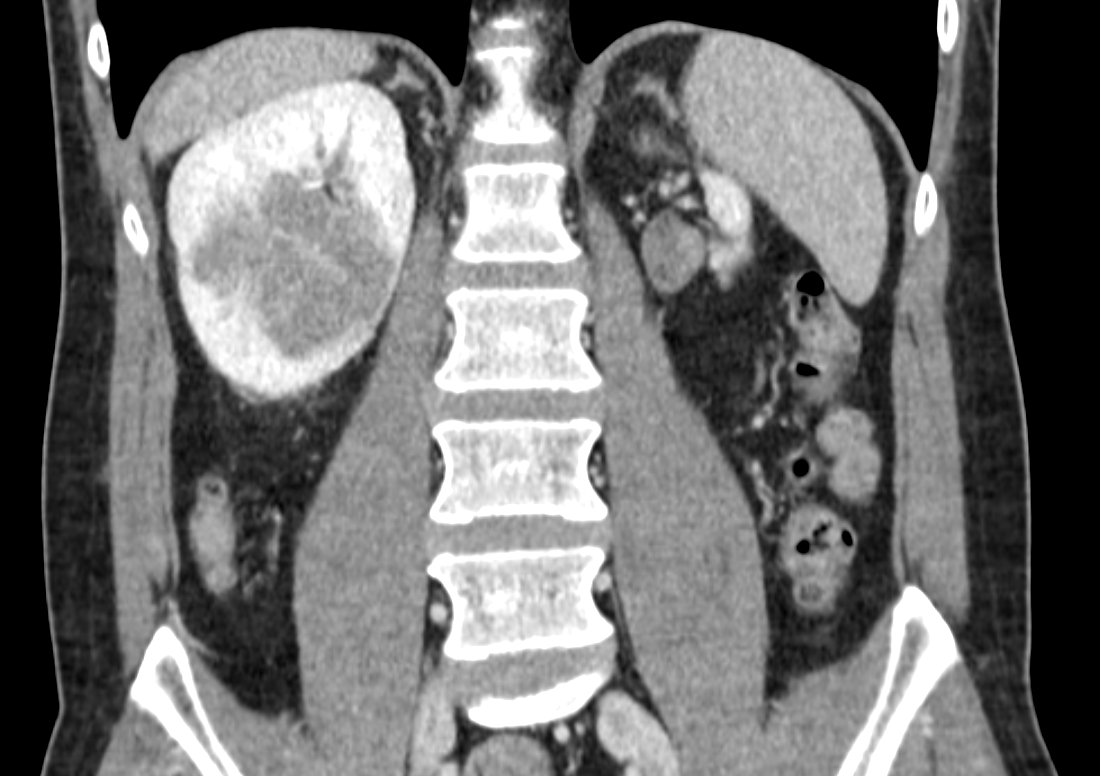

48 years old. 6 cm completely endophytic right kidney mass. Hilar cN1 4 cm. Atrophic left kidney. No symptom, no comorbidity. What to do? #robotics #open #partial #nephrectomy #LND #neoadjuvant #biopsy ???